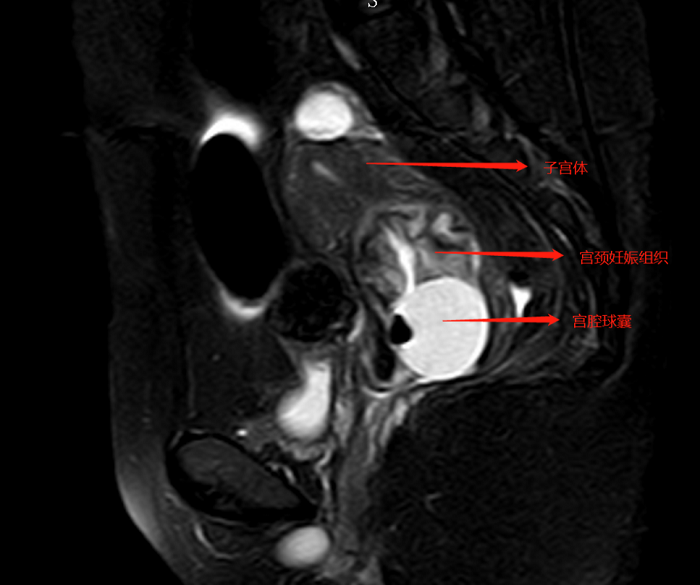

2020-01-16宮頸妊娠反復(fù)大出血,精準診斷治療讓她重拾希望

???? 2020年1月11日,32歲的梁女士從我院婦一科順利出院,這一天對于梁女士及其家人來說意義重大,因為梁女士身上的一顆定時炸彈終于成功摘除了。流產(chǎn)后反復(fù)大出血,她到底怎么了????? 去年10月份,梁女士因“繼發(fā)不孕”在廣州行輔助生...閱讀全文